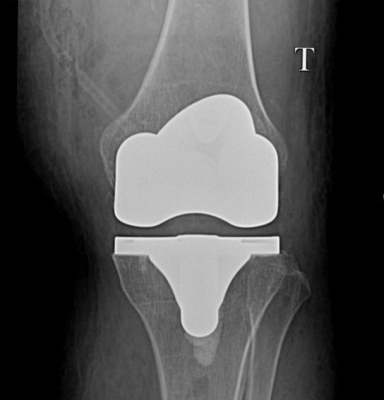

Gần đây nhất là trường hợp chị L.T.L.H 68t ở Duy Xuyên, đau khớp gối 2 bên Trái > Phải nhiều năm, đã điều trị tích cực nội khoa, tiêm nội khớp cũng như phẫu thuật nội soi cắt lọc khớp gối Trái nhưng không cải thiện, khớp gối Trái đau liên tục, đi lại hạn chế, trên X-Quang bắt đầu có biến dạng lệch trục vẹo trong gối, ảnh hưởng đi lại, sinh hoạt cũng như chất lượng cuộc sống. Chị H đã được các bác sĩ khoa Chấn thương chỉnh hình bệnh viện Vĩnh Đức thực hiện phẫu thuật cắt bỏ phần sụn khớp bị hư hại và thay khớp gối nhân tạo chân trái. Hiện sau quá trình phẫu thuật và tập vật lý trị liệu sau mổ, chị đã có thể tự đi lại không cần hỗ trợ, giảm đau khớp gối và không còn nghe tiếng “lạo xạo” mỗi khi hoạt động gấp duỗi gối như trước.

X-Quang sau mổ thay khớp gối toàn phần của BN L.T.L.H